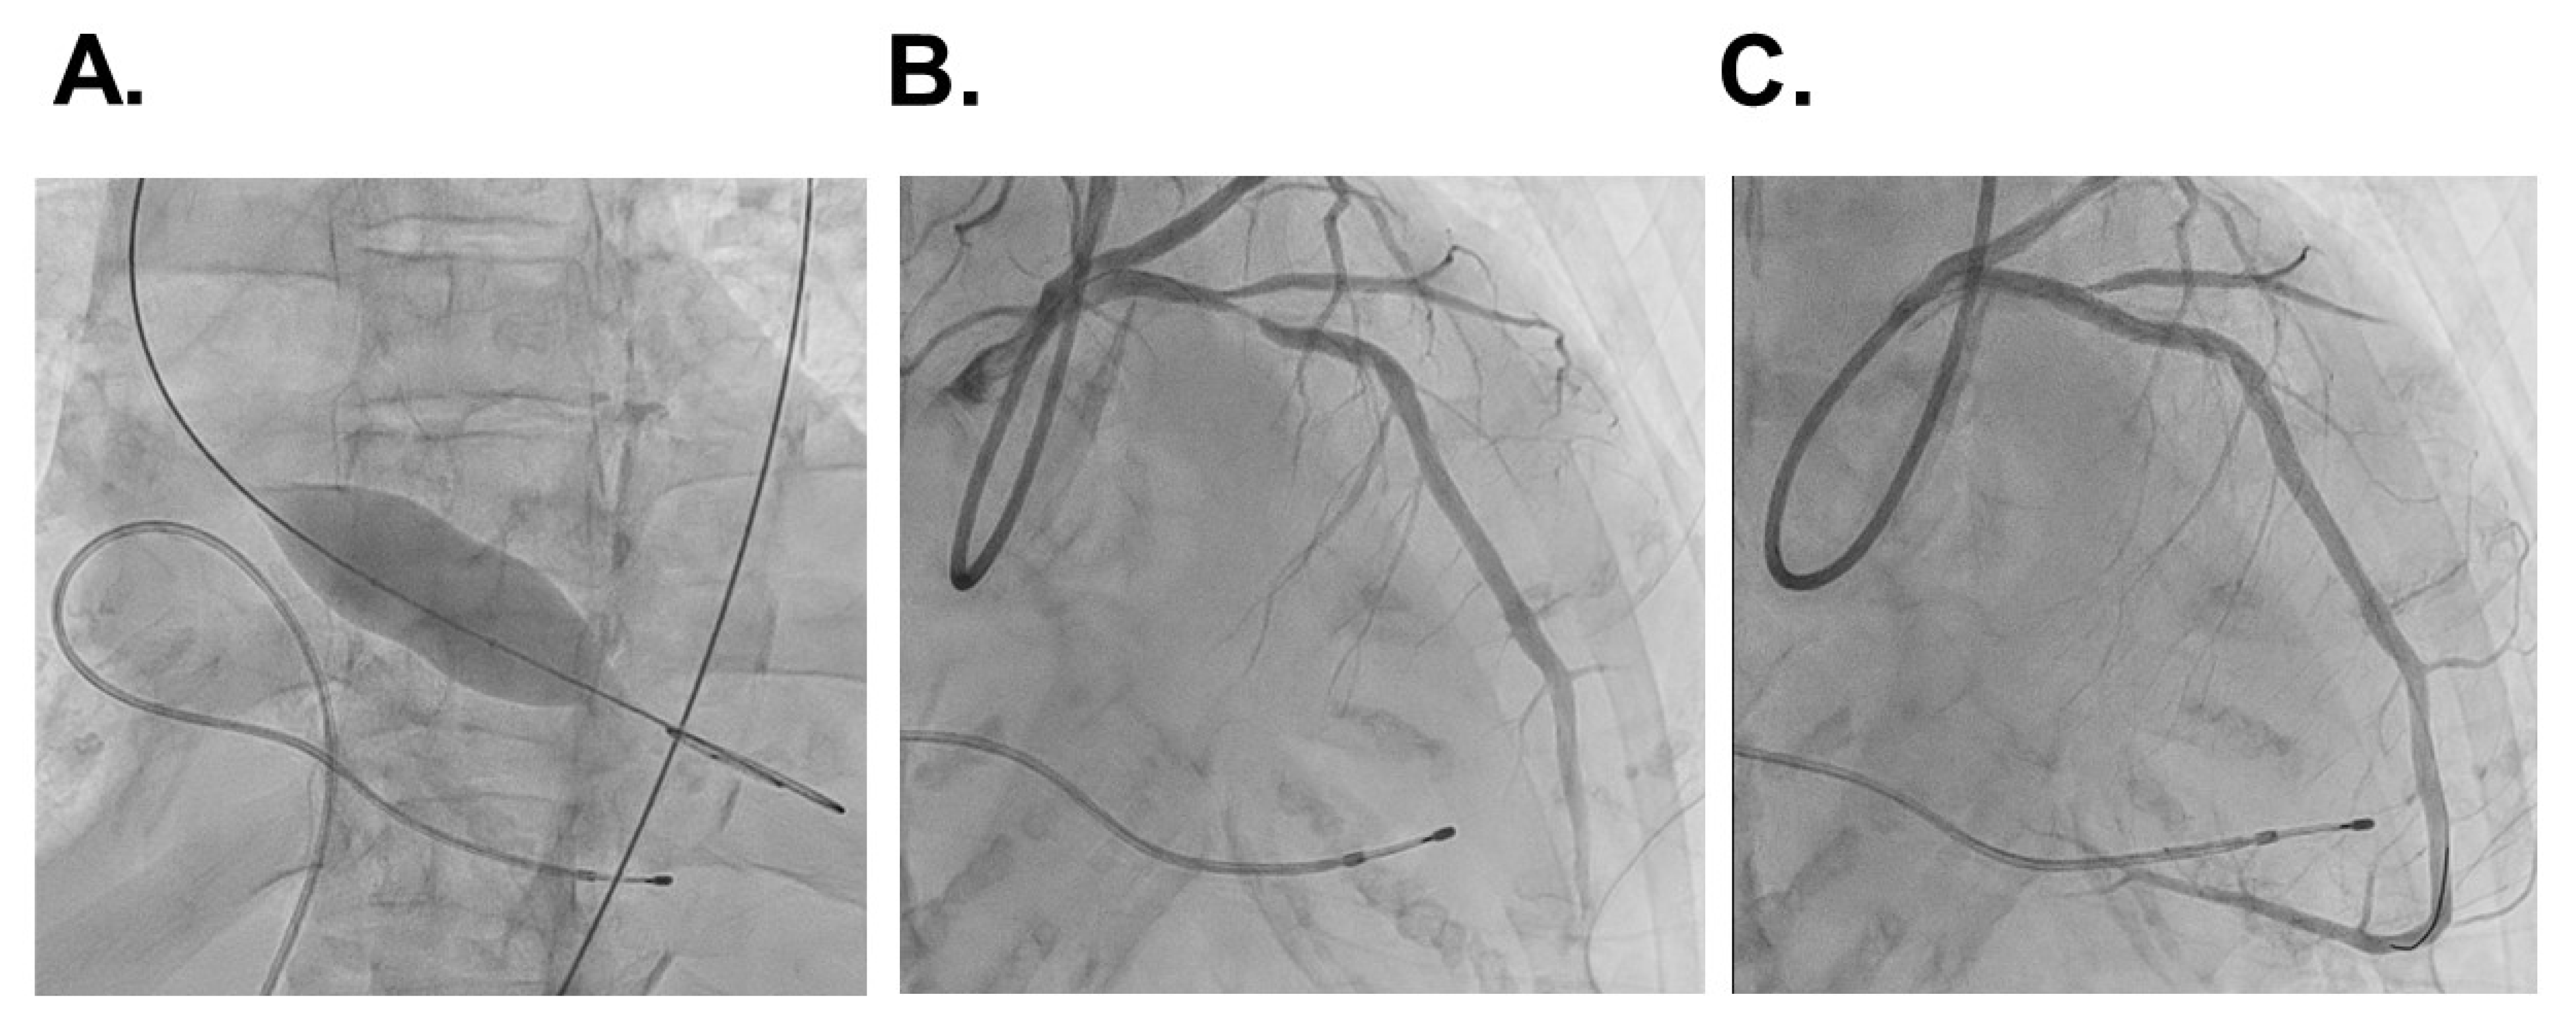

The patient’s body height was 158 cm and his body weight was 46 kg. Systemic blood pressure was 142/84 mmHg and his pulse rate was 94 bpm. The estimated glomerular filtration ratio was 5.4 mL/min/1.73 m2 and plasma B-type natriuretic peptide was 8470 pg/mL. A chest X-ray displayed 61% of cardiothoracic ratio with bilateral mild pulmonary congestion (Figure 1A). An electrocardiogram depicted the sinus rhythm and slight ST depression in V5,6 (Figure 1B).

Figure 1. Chest X-ray displaying cardiomegaly, bilateral pulmonary congestion, and bilateral pleural effusion (A) and electrocardiogram showing heart rate of 64 bpm, sinus rhythm, and ST-segment depression in V5,6 (B) on admission.